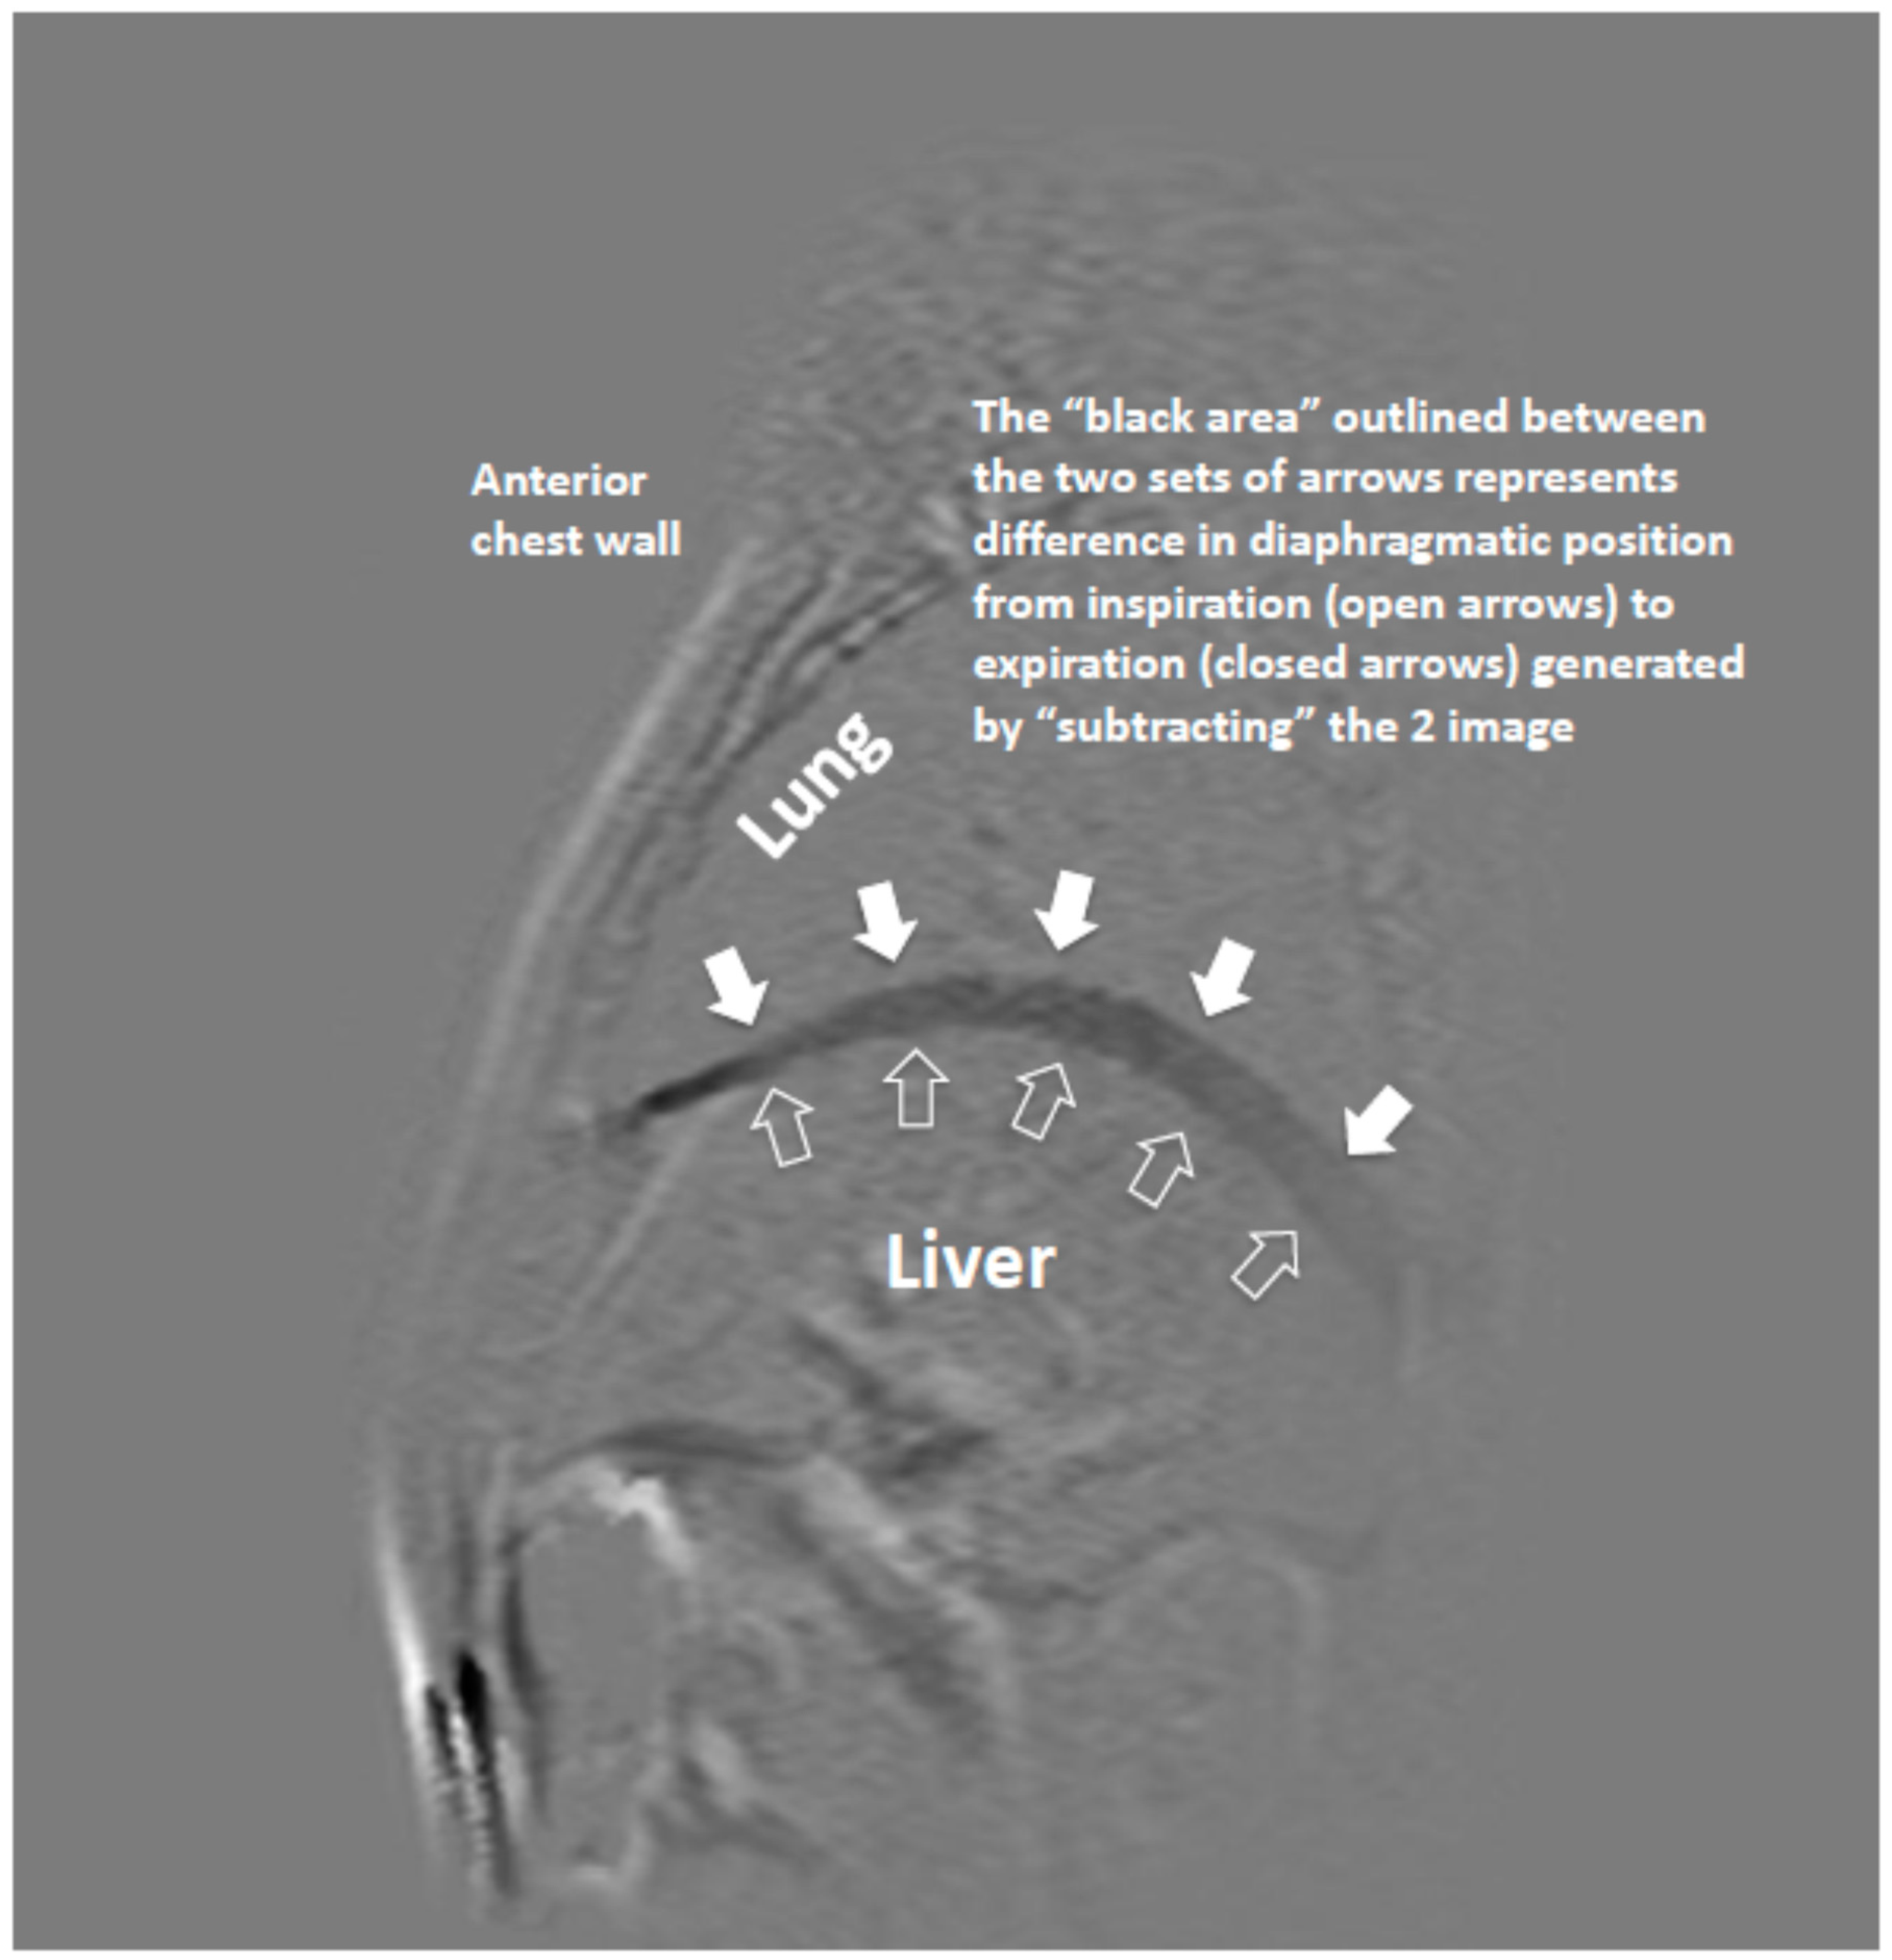

2.2. MR Imaging and Analysis of Diaphragm Motion